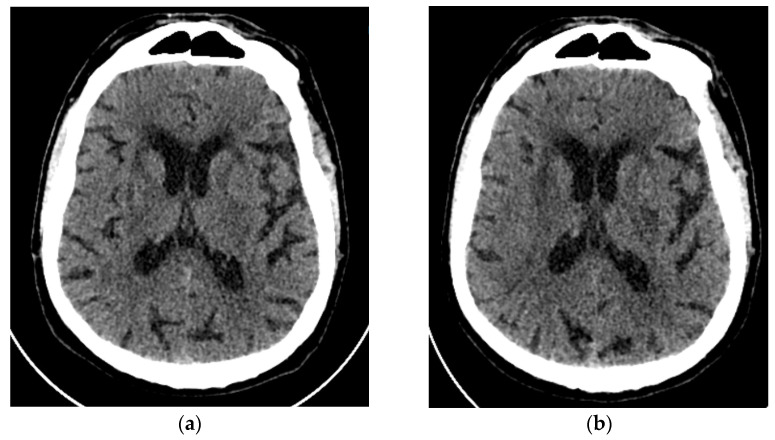

Figure 4.

Axial brain CT scan (a) on an emergency basis with ischemic microangiopathy, without any obvious acute ischemic stroke or hemorrhage; (b) an axial CT scan 2 days later with a hypodense lesion in the left basal ganglia region, on the distribution of the left anterior choroidal artery (AChA) and ischemic microangiopathy periventricular and on the basal ganglia.